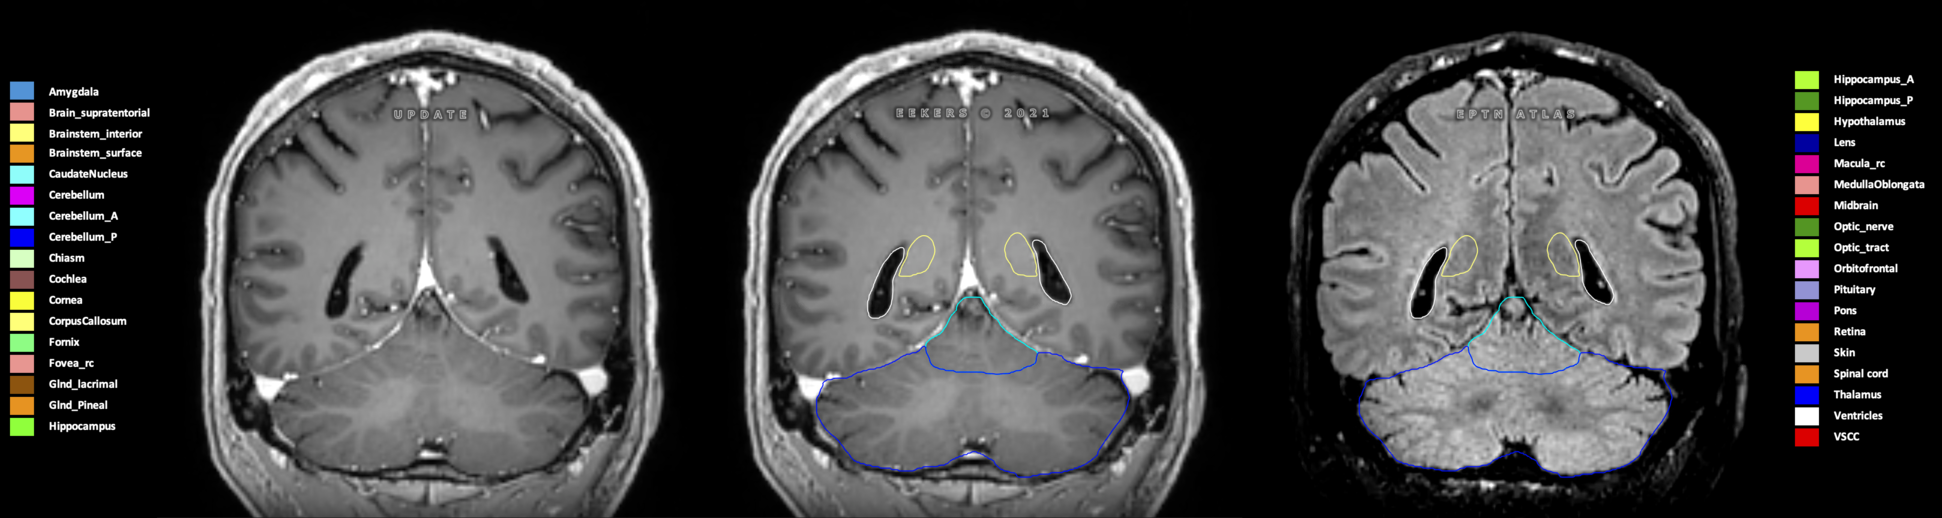

Eekers et al. have published an international neurological atlas for contouring of organs at risk in consensus with the European Particle Therapy Network (EPTN) in 2018 and an update in 2021. The purpose of this consensus atlas is to decrease inter- and intra-observer variability in delineating OARs relevant for neuro-oncology.

Included are all OARs known to be relevant for radiation-induced toxicity in neuro-oncology: brain, brainstem (midbrain, pons, medulla oblongata), chiasm, cerebellum (anterior & posterior), cochlea, cornea, hippocampus (anterior & posterior), hypothalamus, lens, lacrimal gland, optic nerve, pituitary, skin, and vestibular & semicircular canals. To further facilitate research on cognition, vision and radiological changes after irradiation of the brain, potential clinically-relevant OARs are included: amygdala, caudate nucleus, cerebellum (anterior & posterior), corpus callosum, fornix, macula, optic tract, orbitofrontal cortex, periventricular space (PVS), pineal gland, and thalamus.

Three-dimensional delineation of the 25 consensus OARs for neuro-oncology are shown on CT (WW/WL 120/40, 3000/600), 3T MR images, (T1Gd, T2FLAIR 1mm) and 7T MR (MP2RAGE 0.7 mm). All are presented in transversal, sagittal and coronal view.